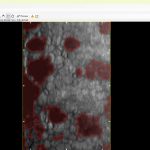

Depuis 2021, ADCIS contribue au projet EviRed, l’un des RHU les plus ambitieux en ophtalmologie. EviRed utilise l’intelligence artificielle et l’imagerie multimodale pour établir une nouvelle classification de la rétinopathie diabétique afin d’améliorer le diagnostic, la prédiction et le traitement du patient :

• Intelligence artificielle : combine l’expertise en apprentissage profond du laboratoire LATIM et des ingénieurs d’ADCIS

• Multimodalité : comprend la photographie du fond de l’œil à champ ultra large, la tomographie par cohérence optique, l’angiographie OCT

• Recrutement d’une cohorte de 3 000 patients par 12 centres de recrutement et suivi des patients pendant 2 ans

• Un centre de lecture dédié a été créé pour soutenir le projet et annoter les images qui serviront de base à l’entraînement des algorithmes d’apprentissage profond

Les rôles d’ADCIS et d’Evolucare dans EviRed consistent à fournir l’ensemble du processus de diagnostic : logiciel d’annotation, visionneuses spécialisées multimodales, algorithmes d’apprentissage profond, infrastructure informatique du projet